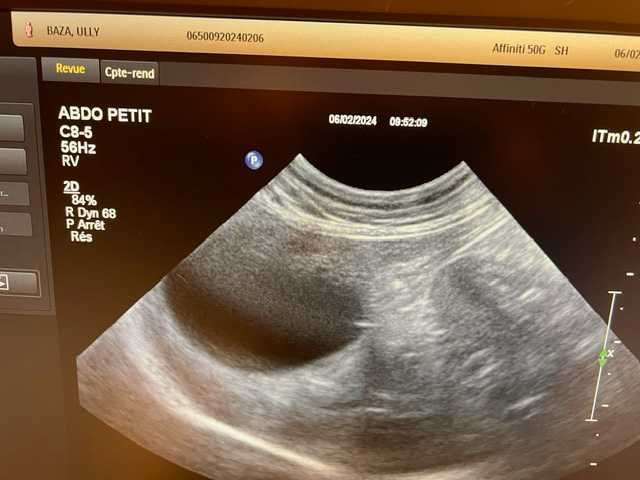

강아지가 목줄을 하고 산책 중에 갑자기 집에 가려고 차도로 뛰어드는바람에 교통사고가 났습니다. 천천히 달려오는 차에 부딪히기는 했지만 걱정돼서 바로 병원으로 갔고 엑스레이, 초음파, 혈액검사 다 시행했지만 이상이 없다고 얘기했습니다. 그런데 사고 이후로 계속 토를 해서 병원에 가서 구토약이랑 진통제를 받아와서 먹였는데도 계속 구토를 하네요ㅠ 사료를 그대로 토하는데 이게 스트레스때문인지 아니면 검사상에 이상이 있는지 여쭤보고 싶어서 글 남깁니다. 또한 가슴쪽을 부딪혔는데 흉부 엑스레이 상에서 이상소견이 있는지 확인 좀 부탁드립니다.

초음파 검사의 경우 초음파를 직접 본 사람이 아니면 찍어놓은 사진으로는 아무런 판단을 할 수 없고 해서도 안됩니다.

주치의의 판단이 가장 정확한 판단이겠으나 지현형으로 장기 손상이 일어나는 경우가 종종 있기 때문에 증상이 지속된다면 복부 초음파 검사를 다시 받아볼 필요가 있어 보입니다.